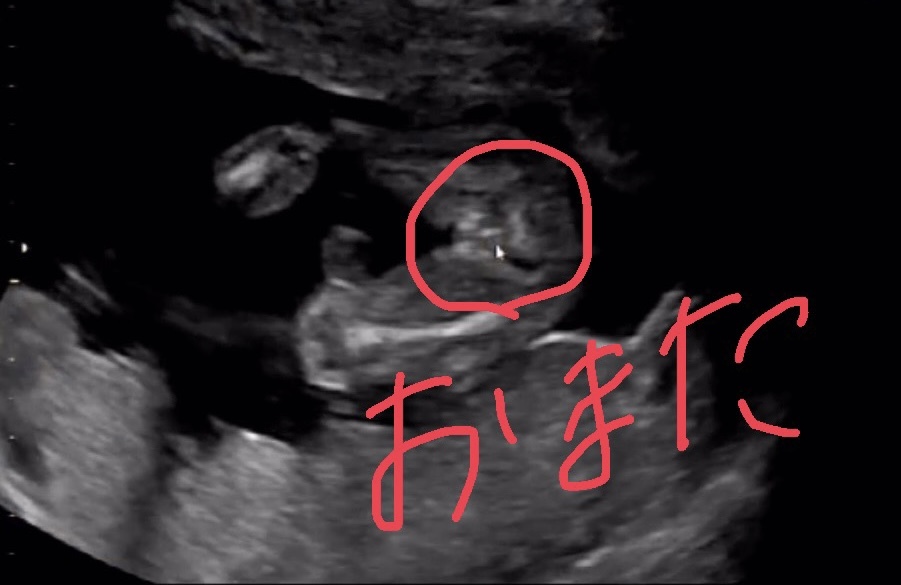

Jul 16, 14 · こんにちは。 今妊娠19週目の妊婦です。 12週の経膣エコーで股の方に女の子の象徴であるコーヒー豆のような形をした部分を発見しました。写真にも残っています。 しかしそのときは先生にはまったく何も言われませんでした。次のエコーの時には、女の子の判定判断ともされる、いわゆる「コーヒー豆」が見えても 中々確定が頂けません。 そして妊娠8ヶ月頃にようやく あ~、やっと分かった〜!と、スッキリした気持ちでいっぱいでした。残念ながら我が家に女の子はいないので、とてもわかりやすい画像をゼクシィbabyよりお借りしました。 女の子の場合、 会陰部に"木の葉マーク"や"コーヒー豆"のような真ん中に何かしらの線が入っていることで判断 されます。

男の子はピーナツ状の突起物、女の子は木の葉やコーヒー豆が股間に見えますが、ときには判定間違いも起こります。 消化管のエコー (超音波)検査のテキスト bechi 消化管エコーのスキルアップに!女の子 エコー コーヒー豆 画像 女の子 エコー コーヒー豆 画像 のランキングをご紹介。エコー タマタマ 木の葉 , 陰嚢や睾丸(タマタマ)がみえる 大きく成長してくると、 陰嚢やその中にある睾丸(精巣)がエコーに映る ことがあります。 陰嚢だけをみると、女の子の特徴とされている木の葉型やコーヒー豆と見紛うことがありますが、その中に白い円形のものが写っていれば

女の子のエコー写真の特徴2:三本線 女の子のエコー写真の特徴2つめは、三本線です。女の子の場合は、股の割れ目と大陰唇で見分けることができます。 この割れ目が女の子の外性器です。 三本線やコーヒー豆などと表現されることもあります。